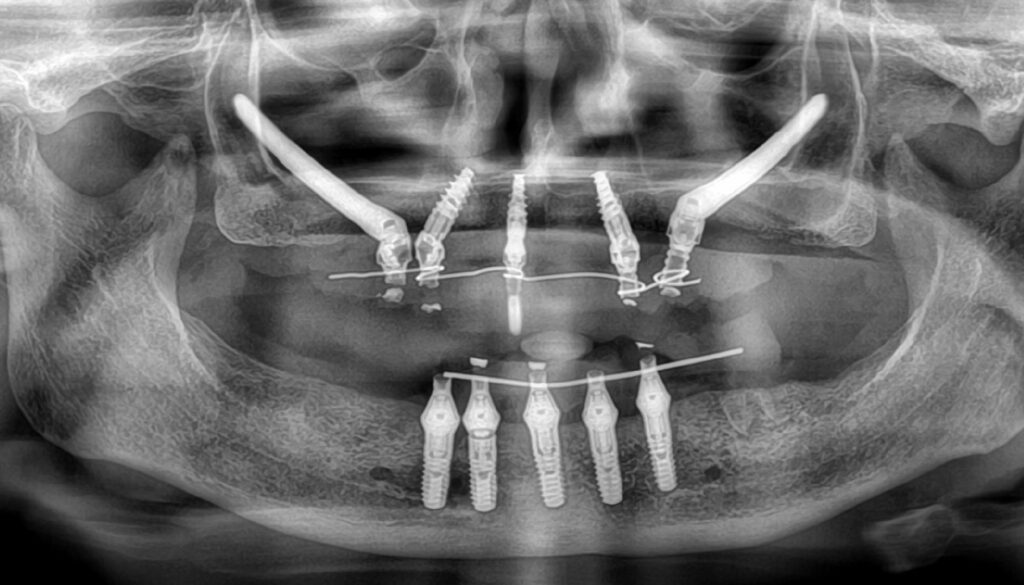

Full mouth rehabilitation involves replacing all of your teeth-in either the upper or lower arch, or both-using strategically placed dental implants that support a fixed set of natural-looking teeth.

Led by Dr. Praveen Rajesh (MDS, M Endo RCS – UK), our team takes a comprehensive, precision-driven approach to full mouth rehabilitation. We use 3D scans, microscopes, and custom prosthetic design to rebuild your smile from the ground up-ensuring function, aesthetics, and long-term comfort.